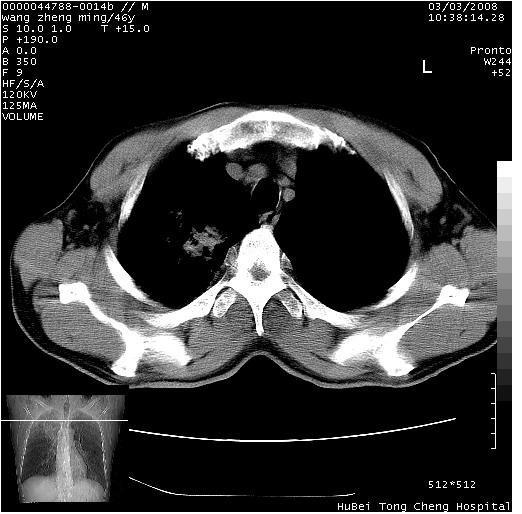

以下是引用卜一在2008-3-22 1:37:00的发言:[br]右肺实质性肿块,边缘不整,明显见毛刺征 分叶征及胸膜凹陷征,右上叶支气管明显变窄,远端散在的片状 斑片状实变影。另:左肺门较大肿块,支气管受累 变窄,远侧见阻塞性肺炎。纵隔内见肿大淋巴结。多考虑:右肺周围性肺癌伴左肺门 纵隔淋巴结转移!